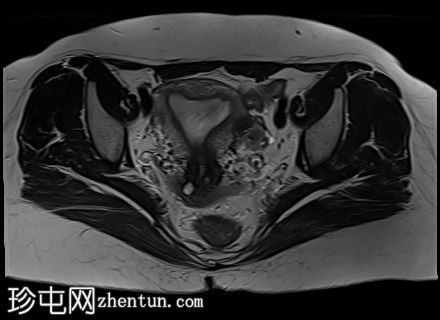

轴位

T2加权像

5.jpg

增大的子宫腹股沟区(AVF)显示:

子宫前壁交界区局灶性增厚,边界不清。形成直径约3厘米的局灶性肿块样病变,轻度压迫膀胱。肿块边界模糊不清,可见多个细小出血灶,在T1加权像和T2加权像上均呈高信号,提示局灶性子宫腺肌症。

子宫体前壁可见另一处病灶,位于上述病灶尾侧,边界清晰(有包膜)。该病灶在T1和T2加权像上均呈低信号,内部未见异常信号灶,周围可见少量明显血管通道,提示为小型子宫肌瘤。

子宫内膜厚度正常。

宫颈MRI表现正常,可见少量纳博氏囊肿。

左侧卵巢可见数个小囊肿,在T1加权像上呈高信号,在T2加权像上呈低信号(T2阴影),T1脂肪抑制序列未见信号下降,提示其为血液降解产物。最大的囊肿轴位大小约为3.1×1.7 cm,轻度压迫卵巢实质。

右侧卵巢可见黄体囊肿。未见实性肿块。

盆腔少量游离液体。